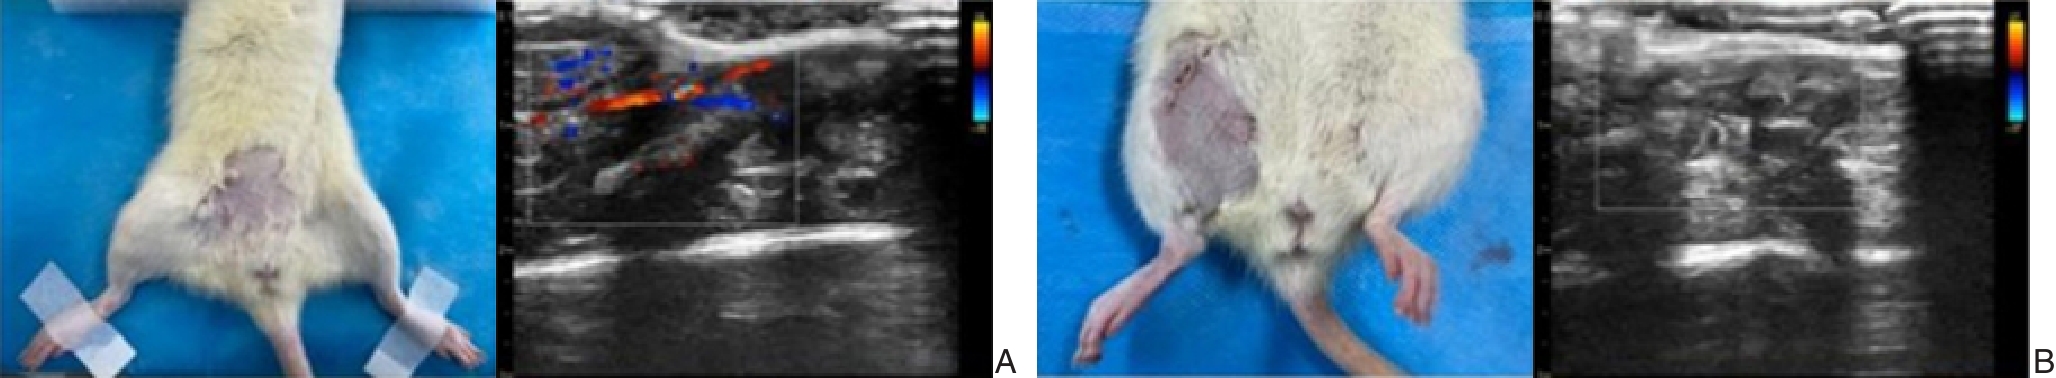

摘要:背景与目的 研究显示,长链非编码RNA(lncRNA)FGD5-AS1在胃癌(GC)中发挥致癌基因的作用。笔者前期通过生物信息学分析发现,FGD5-AS1与微小RNA-142-3p(miR-142-3p)、miR-142-3p与丙酮酸脱氢酶激酶1(PDK1)之间存在结合位点。因此,本研究探讨FGD5-AS1靶向miR-142-3p/PDK1对GC细胞中的表达及作用。方法 利用双荧光素酶报告基因实验验证FGD5-AS1与miR-142-3p、miR-142-3p与PDK1之间的靶向关系。采用qRT-PCR检测GC组织中FGD5-AS1、miR-142-3p和PDK1的表达水平。构建sh-FGD5-AS1干扰体系及miR-142-3p抑制模型,分别或联合转染GC细胞系BGC823,观察细胞增殖(CCK8、EdU)、凋亡(流式细胞术)、迁移与侵袭(Transwell)等生物学行为及相关蛋白表达(Western blot)。通过裸鼠皮下成瘤实验检测FGD5-AS1对GC移植瘤生长的影响。结果 双荧光素酶报告基因实验显示,miR-142-3p mimic可明显降低FGD5-AS1和PDK1野生型(WT)报告基因的荧光活性(均P<0.05),而对突变型(MUT)无影响,证实FGD5-AS1与miR-142-3p、miR-142-3p与PDK1之间存在直接结合关系。敲除FGD5-AS1后,GC细胞中miR-142-3p表达上调,PDK1表达下调,细胞增殖、迁移、侵袭能力减弱,凋亡增强,上述变化可被miR-142-3p抑制剂逆转(均P<0.05)。动物实验显示敲除FGD5-AS1可明显抑制裸鼠移植瘤的生长及移植瘤组织中Ki-67、PDK1表达(均P<0.05)。结论 FGD5-AS1可能通过ceRNA机制靶向吸附miR-142-3p,从而解除对PDK1的抑制,促进GC细胞的增殖与侵袭,并加速肿瘤生长。FGD5-AS1/miR-142-3p/PDK1轴在GC发生发展中发挥关键作用,或可作为潜在的诊疗靶点。